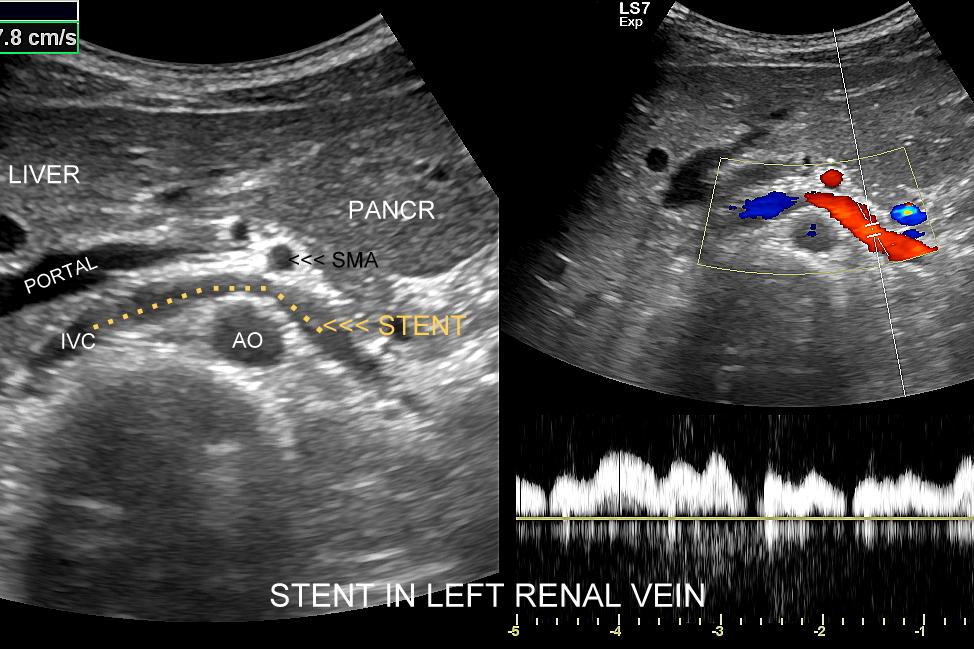

Inne wskazania do przeprowadzenia diagnostyki USG przepływów nerkowych obejmują ocenę funkcji nerek w przebiegu chorób ostrych oraz przewlekłych, takich jak nefropatia cukrzycowa, glomerulopatie, czy zapalenia kłębuszków nerkowych. Badanie USG Doppler wykonywane jest również przy podejrzeniu zakrzepicy żyły nerkowej i zespołu „dziadka do orzechów”; przy stwierdzeniu obecności żylaków powrózka nasiennego u mężczyzn; żylaków miednicy u kobiet; w sytuacjach, gdy podczas standardowego badania USG jamy brzusznej uwidoczniono patologię nerki (np. guz nerki, marskość); a także przy stwierdzeniu podwyższonych wartości parametrów nerkowych w badaniach laboratoryjnych (kreatynina, mocznik, cystatyna C, potas) oraz w ramach oceny USG nerki przeszczepionej.